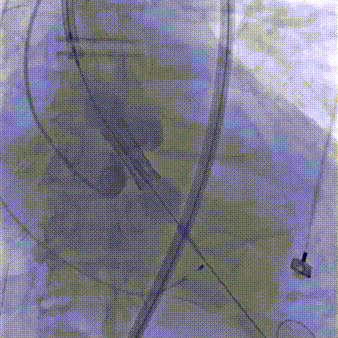

造影下瓣膜定位;

瓣膜定位

瓣膜定位.